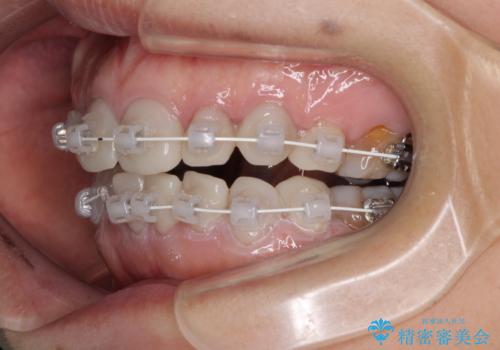

- 小さいころからの歯の変色と矯正治療の後戻りを気にして来院された患者様です。

気になる変色歯を仮歯に変え、その後歯列不正を矯正治療で改善し、最後にオールセラミッククラウンにて補綴治療することとしました。

数十年に及んだ歯の変色が改善されたため、大変満足していただきました。